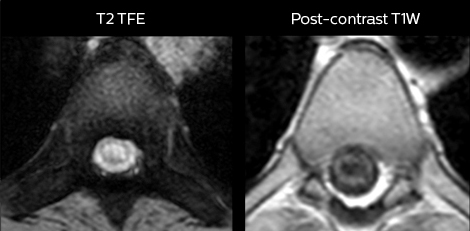

To minimize the time taken to perform scans, rapid MRI examination protocols (ExamCards) were developed, shortening the total scanning time to even less than 10 minutes in some exams. Techniques like mDIXON (modified DIXON) are used for robust capturing of fat-free MRI images in a hectic ED environment.

in image acquisition and postprocessing algorithms.”“mDIXON TSE sequences allow simultaneous characterization of morphological changes from the in-phase T2-weighted images and visualization of edematous changes, thanks to the water T2-weighted images from the same acquisition. Anatomical and morphological considerations could be a partial or complete ligament tear, a bony avulsion or hematoma.”

“For soft tissue assessment mDIXON brings similar benefits. For example in one T2-weighted mDIXON TSE acquisition, having the multiple contrasts helps us assess abnormalities in peripheral nerves fascicles, which may be due to anatomical or inflammatory changes..”

“mDIXON is robust with regard to susceptibility type of problems that would come up with traditional spectral fat-saturated images.”